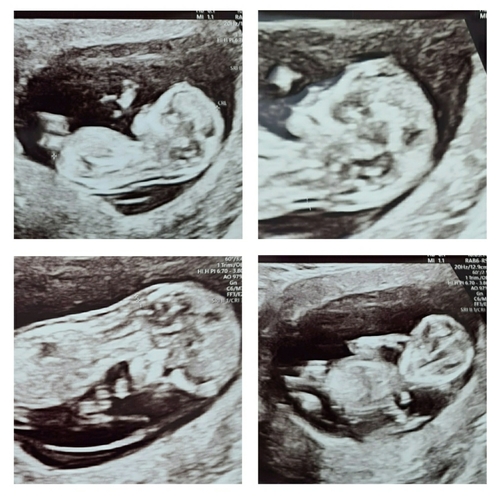

Je kan best al veel zien! Dit waren enkele plaatjes van mijn 12 weken echo. Ik was toen ook exact 12 weken zwanger